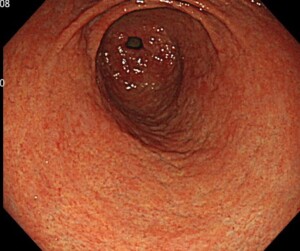

当院では、胃カメラを受けた際には、「ピロリ菌がいない胃」、「ピロリ菌がいた胃(除菌後)」、「ピロリ菌がいる胃」、「ピロリ菌がいるかいないか微妙な胃」なのかご説明します。

*萎縮性胃炎あり(ピロリ陽性)

*萎縮性胃炎なし(ピロリ陰性)